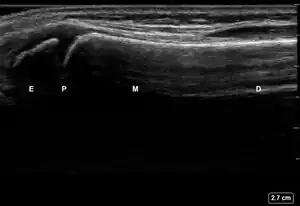

| 6 View Technique for Ultrasound Scanning of Pediatric Distal Forearm Fractures | # | Procedure Step | Reference Multimedia |

| 2 | Obtain, label, and save an image of the epiphysis (E), physis (P), metaphysis (M), and diaphysis (D). | ![]() | |